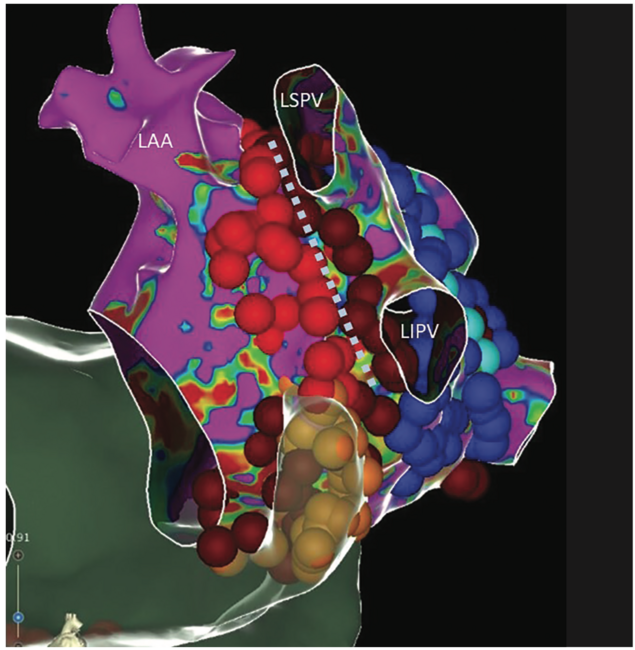

Elimination of a perimitral atrial flutter circuit can be particularly challenging and incomplete linear ablation may perpetuate flutter; therefore, we do not recommend routine mitral isthmus ablation except when inducible or in the presence of advanced atrial fibrosis. All available approaches present challenges, again due to difficulty achieving lesion transmurality. The 2 main strategies for achieving mitral block are an anterior line connecting either the right or left superior PV antrum to the anterior mitral annulus superior to the left atrial appendage (LAA), or a lateral line connecting the left PV antra to the lateral mitral annulus inferior to the LAA. The anterior path is hindered by Bachmann’s bundle, the thickest portion of the human atrium. If endocardial block is achieved without block across Bachmann’s bundle, a biatrial reentry circuit can be observed. This has been verified in epicardial mapping studies.29,30 When endocardial ablation of Bachmann’s bundle cannot be achieved and flutter persists, options are creation of an alternate mitral line or epicardial ablation. A portion of the anterior left atrium can be reached from the pericardial space, though the aortic root limits accessibility to the region near the right PVs. For this reason, our usual approach is a lateral line. The 2 challenges in the lateral approach are the coronary sinus (CS) and VOM. When ablating along the lateral mitral annulus, blood flow through the CS reduces epicardial tissue heating via convective loss of energy.31 Because of this, epicardial ablation within the CS itself is nearly always required to achieve lateral mitral block. In some instances, the CS musculature itself may serve as a bridge over a lateral mitral line (Figure 1). This problem can be easily addressed by ablation within the CS, and at times, circumferential ablation is needed. A more challenging problem is epicardial bridging utilizing the VOM (Figure 2)32, which can actually cause the lateral mitral annulus adjacent to the line of block to become a passive part of the flutter circuit (Figure 3, Video 1). Our strategy to address this is to ablate both the anterior and posterior aspects of the left lateral ridge from the level of the superior to inferior PVs (Figure 4). If this does not abolish VOM conduction, then targeting the touch down area of the VOM may be effective (Figure 5). If endocardial approaches are not effective, VOM ethanol infusion is very likely to be successful but has some risk of perforation and pericardial bleeding. Finally, ablation from the pericardial space along the sulcus between the left PVs and LAA can be performed. Systematic ablation of the VOM by ethanol infusion has shown promising results.33-35

Video 1. Activation map of perimitral flutter following attempted creation of a lateral mitral line. Activation demonstrates an endocardial line of block between the left inferior pulmonary vein and the mitral valve. Activation emerges at the top of the left lateral ridge suggestive of conduction up the VOM.